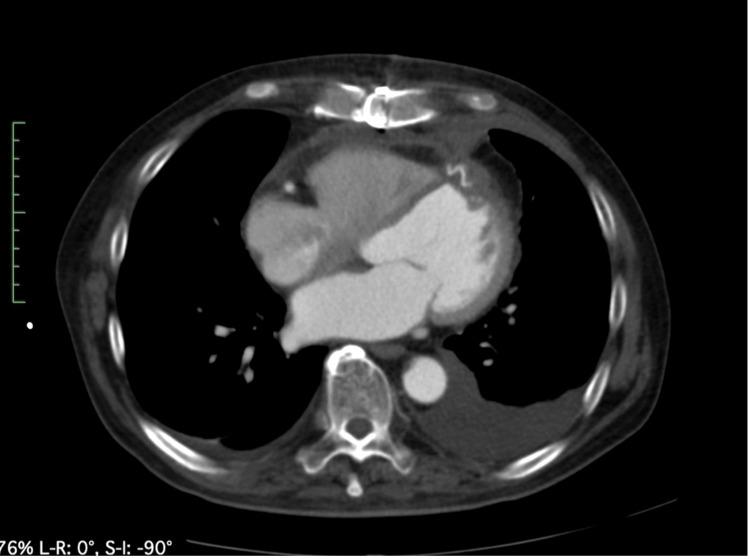

A 66-year-old male patient underwent repair using the sutureless technique for an oozing-type cardiac rupture associated with myocardial infarction of the anterior left ventricular wall. On postoperative day 10, echocardiography revealed a thrombus in the apex region, and anticoagulation therapy was started with warfarin. The thrombus disappeared two months postoperatively. Four months after surgery, the patient came to the hospital with a chief complaint of breathlessness. The computer tomography scan showed a pseudoaneurysm in the left ventricular anterior wall. Because of breathlessness due to decreased effective cardiac output associated with the left ventricular mass and the risk of rupture of the left ventricular pseudoaneurysm, we decided that surgery was indicated. When the left ventricular pseudoaneurysm was incised under cardiac arrest using an artificial heart-lung machine, an oval-shaped communication orifice was found, which was closed directly with continuous sutures. The breathlessness disappeared and the patient was discharged 13 days after surgery.

一名66岁男性患者因左心室前壁心肌梗死伴渗出型心脏破裂,采用无缝合技术进行修复。术后第10天,超声心动图显示心尖区域有血栓形成,遂开始使用华法林进行抗凝治疗。术后两个月血栓消失。术后四个月,患者因呼吸困难为主诉前来医院就诊。计算机断层扫描显示左心室前壁有假性动脉瘤。由于左心室肿块导致有效心输出量减少引起呼吸困难以及左心室假性动脉瘤破裂的风险,我们决定进行手术。在使用人工心肺机使心脏停搏的情况下切开左心室假性动脉瘤时,发现一个椭圆形的交通口,用连续缝合直接将其封闭。呼吸困难消失,患者术后13天出院。